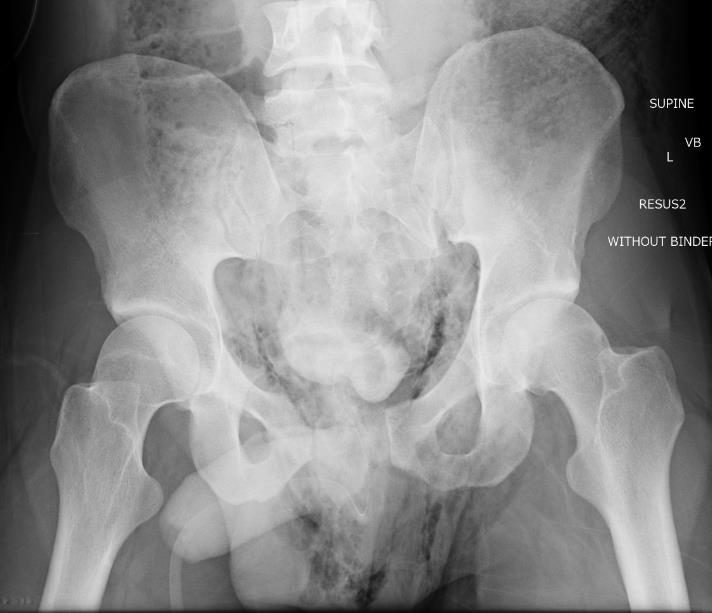

Retrograde urethrogram indicated for blood at meatus +/- retropubic catheter

Pelvic Fracture Retrograde Urethrogram Normal

Retrograde urethrogram in setting of APC pelvic fracture